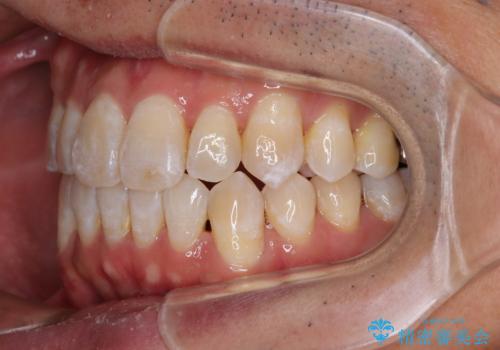

- 前歯のデコボコとクロスバイトを気にして来院された患者様です。

40代半ばであり、あまり周りに気を遣われずに治療を進めたいとのことで、インビザラインにて矯正治療を行うこととしました。

毎日22時間の装着時間をきっちりと守ってくださり、1年半かけずに思い通りの歯列に仕上げることができました。